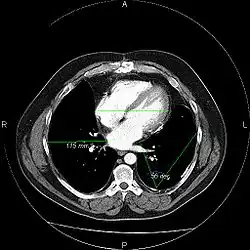

Picture Archiving and Communication System, afgekort als PACS, is een beeldverwerkend systeem (computers en servers in een netwerk met specifieke software) dat het mogelijk maakt om via computers de digitale beelden (met verslag) gemaakt op de afdeling radiologie, te verwerken, te archiveren en te verspreiden bij de aanvragende medisch specialisten.

Het PACS is een applicatie primair bedoeld voor de radioloog. Maar door het digitale karakter van het systeem is het ook mogelijk dat anderen dan radiologen toegang hebben of krijgen tot de digitale PACS-beelden. In het PACS worden alle digitale radiologische beelden volgens een speciaal protocol, DICOM, opgeslagen die zijn geacquireerd op de modaliteiten (of radiologietoestellen). Middels standaardkoppelingen, zoals HL7, worden de juiste patiëntengegevens van het ZIS (Ziekenhuis Informatie Systeem) naar het PACS gestuurd. Er zijn PACS-systemen die volledig zijn geïntegreerd met het RIS (radiologie informatiesysteem). Door deze PACS-RIS-koppeling ontstaat er een complete radiologische workflow waarbij de juiste patiëntengegevens (uit het ZIS) met de juiste beeldgegevens worden gekoppeld. Op het secretariaat worden de afspraken van de patiënten in een lijst gezet. De verschillende modaliteiten (röntgenapparaat, MRI-scanner, CT-scanner, e.d.) kunnen hun eigen werklijst (de zogenaamde DICOM Modality Worklist, oftewel DMWL) opvragen, hierdoor is er een vlotte doorstroming van alle informatie naar de modaliteiten, dokters en verpleegkundigen, waardoor:

- De digitale radiologische beelden door meerdere artsen tegelijkertijd te bekijken zijn.

Indien de patiënt al eerder voor röntgenonderzoek is geweest, kunnen ook deze afbeeldingen opgevraagd worden (indien deze digitaal opgeslagen zijn). Hierdoor kan vergeleken worden met vorige onderzoeken (bv. effect van chemotherapie, genezing van pneumonie of fractuur) of kunnen meerdere onderzoeken bij dezelfde patiënt (bv. echo en CT) samen bekeken worden.